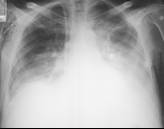

Erect

In the supine position, the fluid layers out posteriorly and produces a

haziness, especially near the bases (since the patient is actually semi-

recumbent). In the erect position, the fluid falls even more to the bases.